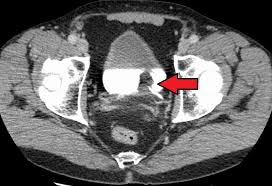

What Are The First Signs Of Bladder Cancer In A Man - Bladder Cancer Practice Essentials Background Anatomy / You may notice streaks of blood in your urine or the blood may turn your urine brown.. The most common form of bladder cancer is known as urothelial carcinoma because it starts in the urothelial cells within the lining of the bladder. Bladder cancer occurs most often in the lining of the bladder, the pelvic organ which stores urine. For most people, the first symptom of bladder cancer is blood in the urine, also called hematuria. Early signs of bladder cancer. If there is enough blood it can change the color of the urine to be orange, pink, or darker red.

The signs and symptoms of bladder cancer can vary based on the size and location of the tumor as well as the stage of the disease. Bladder cancer signs and symptoms may include: In 2019, around 4.6% of all new cancer cases were bladder cancer. Blood in urine (hematuria), which may cause urine to appear bright red or cola colored, though sometimes the urine appears normal and blood is detected on a lab test Bladder cancer signs and symptoms 1.

You may notice streaks of blood in your urine or the blood may turn your urine brown. It's important to understand that the early signs and symptoms of bladder cancer are often intermittent and not severe. There may be enough blood to change the color of the urine to orange, pink, or, less often, dark red. For most people, the first symptom of bladder cancer is blood in the urine, also called hematuria. Irritation when urinating, urgency, frequency and a constant need to urinate may be symptoms a bladder cancer patient initially experiences. Gross hematuria means you can see the blood in your urine, which may appear pink, red, or brownish in color. Knowing the signs and symptoms can help you get diagnosed sooner, which may improve your prognosis. When caught early, bladder cancer is highly treatable, so understanding these signs is important for the best prognosis. The early stages of bladder cancer can cause bleeding with little or no pain. The early signs of bladder cancer are related to a tumor that has not yet metastasized. This may cause changes to the colour of the urine, such as turning it orange, pink or red. The most common sign of bladder cancer is blood in the urine (pee) (hematuria). Bladder cancer signs and symptoms 1.